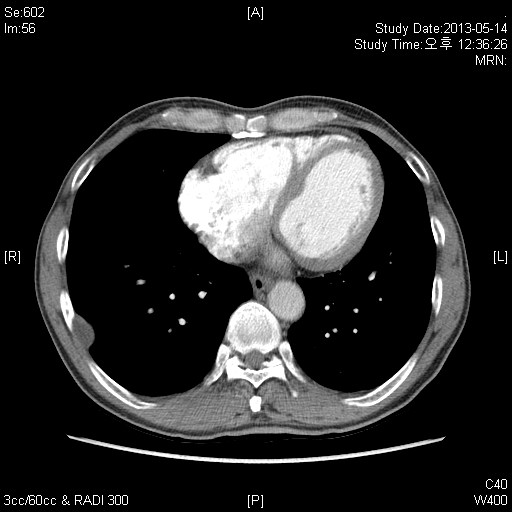

59¼¼ ³²È¯ ƯÀÌ ³»°úÀû °ú°Å·Â ¾ø´ø ȯÀÚ·Î °Ç°­°ËÁøÀ¸·Î ½ÃÇàÇÑ CxR »ó ÀÌ»ó¼Ò°ßº¸¿© refer µÈ ȯÀÚÀÔ´Ï´Ù.

³»¿ø´ç½Ã ƯÀÌ Áõ»ó¾ø¾ú°í,³»¿ø ´ç½Ã lab °ú CxR,chest CT ´Â ´ÙÀ½°ú °°½À´Ï´Ù.